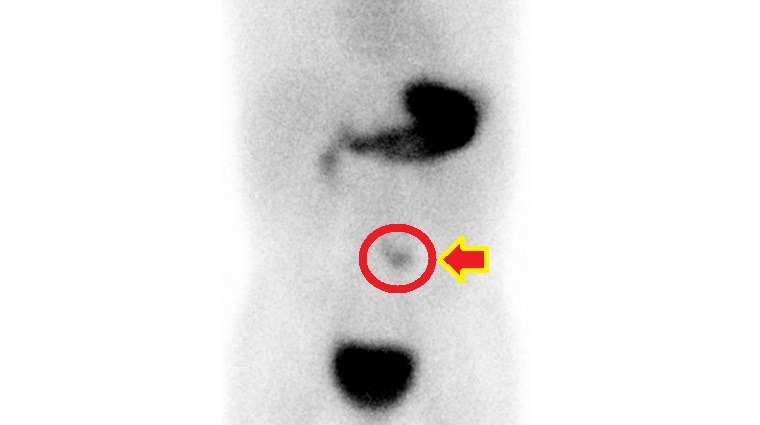

圓圈處為核醫檢查梅克爾憩室顯影處。(圖/台大醫院新竹分院提供)(轉載自/健康傳媒)

梅克爾憩室診斷主要靠梅克爾核醫掃描檢查,顯示異位性胃黏膜組織,若出現臨床症狀,以手術切除為主要治療方式。梅克爾憩室或其併發症因早期症狀不典型,臨床上易與腸胃炎混淆。徐千婷醫師呼籲,若孩子出現大片血便,或嚴重腹痛等異狀,應盡早就醫檢查,及時治療。